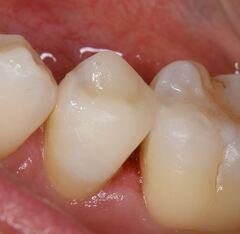

歯は削れば削るほど、もろくなります。歯の表面のエナメル質に無数のひびが入ったり、インレー(歯の詰め物)

(虫歯よりもかなり大きく削る)を装着すると、くさびのような働きをして、歯が割れてしまう事があります。

一時治ったと思っても、長い目でみると歯そのものの寿命を短くしてしまいます。